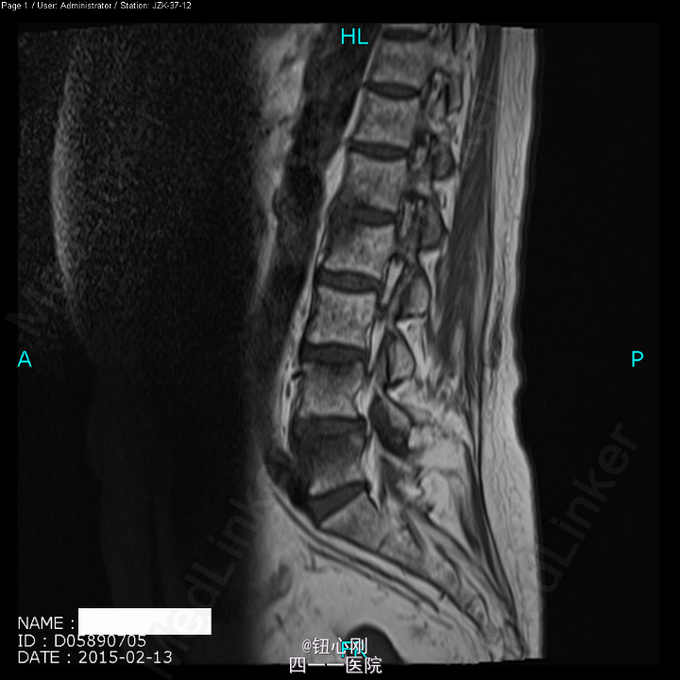

患者, 女,66岁。 主 诉:反复颈肩部麻木感10余年,腰骶痛3月余。 现病史:患者缘于10年前无明显诱因下出现双侧颈肩部轻微麻木及不适感,给予按摩等理疗后好转,此后每年不定期反复发作,未予重视,2月前患者在搬重物后出现腰痛症状,弯腰不能,予以针灸等理疗,症状有所改善。2015年2月13日来我院就诊,行脊柱MRI及PET-CT扫描示:颈6、胸12、腰2、4、5椎体转移瘤?

体检未见明显阳性体征。 辅助检查:血沉68mm/h,神经元特异性烯醇化酶23ug/l,余肿瘤指标正常。三大常规、肝肾功、电解质正常。 颈椎MRI、腰椎MRI及PET-CT扫描见图。

术前诊断:多椎体病变待查(转移瘤?) 诊断依据:老年女性,出现颈腰部疼痛,MRI及PET-CT扫描提示椎体多节段病变,以转移瘤可能性为大,同时血沉升高。 处理:2015-03-31在全麻下行颈6椎体病变前路次全切+钢板钛网植骨融合内固定术。术中所见:颈6椎体骨质疏松,部分硬化,未见鱼肉样组织。术后切除骨质送病理检查。 病理报告:骨小梁稀疏,其间有纤维组织,同时可见硬化死骨。 术后诊断:颈6椎体骨质疏松性骨坏死。

随着医学影像学及脊柱微创手术的发展,骨质疏松性椎体骨坏死逐渐被认识。该病临床上并非少见,骨坏死会导致椎体逐渐塌陷与进行性后凸畸形,引起患者长期腰背痛,甚至出现脊髓神经受压而瘫痪。患者为老年,主诉脊柱疼痛,MRI有椎体信号改变,因而易与脊柱转移性肿瘤混淆。骨坏死椎体在T1WI加权像上呈界限清楚的低信号区域,在T2WI加权像及脂肪抑制序列像上呈界限清晰高信号区域。这是与脊柱转移性肿瘤相鉴别的要点,对于累计整个椎体的骨坏死更需注意鉴别。 如疼痛不缓解或发生后凸畸形,可行椎体后凸成形术。